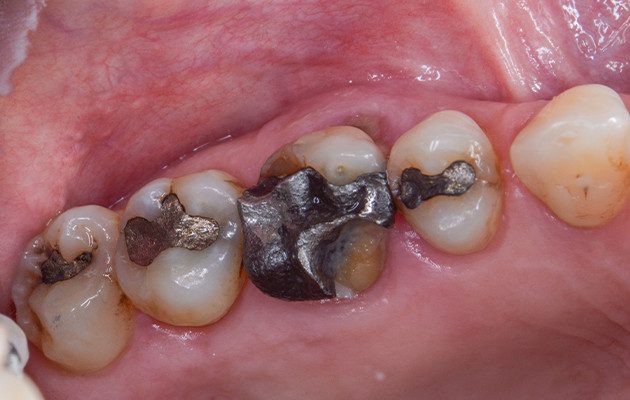

Na avaliação clínica, verificou-se o extravasamento de pus via sulco gengival no dente 16. A paciente relatava dor à palpação local e durante a percussão. Além disso, o dente 16 apresentava mobilidade grau 1, fratura de cúspides, uma extensa restauração de amálgama, lesões cariosas próximas à restauração e acúmulo de biofilme. O exame tomográfico revelou uma lesão envolvendo a raiz mesiovestibular do dente 16, com provável comunicação endoperiodontal.

2 | Vista da superfície oclusal do dente 16. Nota-se a fratura das cúspides do dente, a restauração em amálgama de grande extensão, o acúmulo de biofilme e a presença de cárie abaixo da restauração.